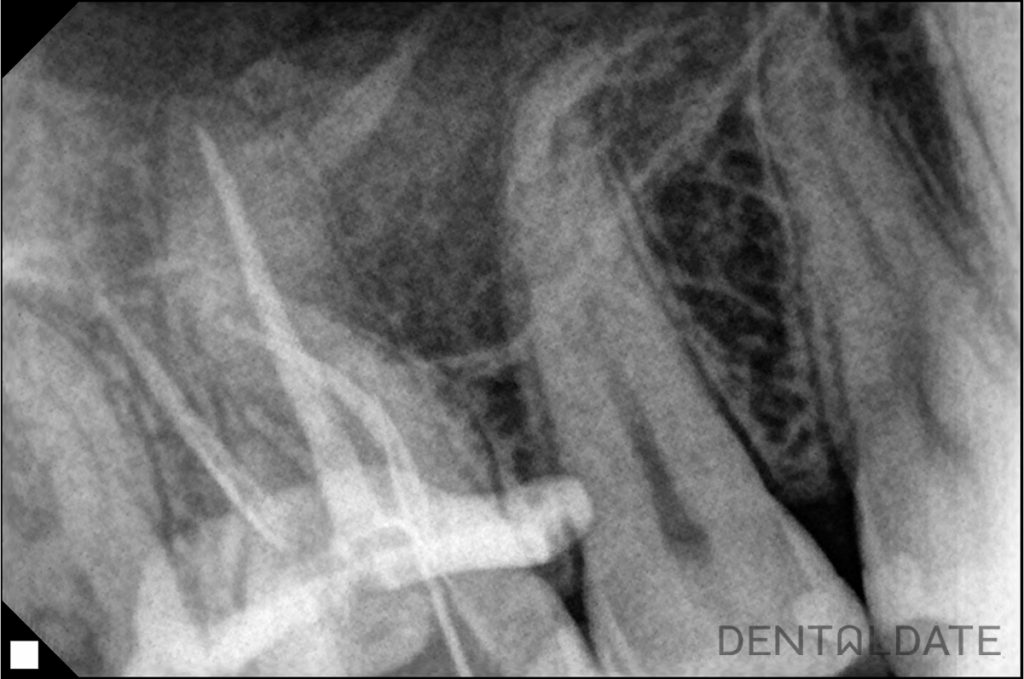

On CBCT: The tooth was previously treated endodontically in another clinic. The medial cheek root has a complex curve in the apical third. The canals are obturated to the apex. In the periapical tissues of the medial cheek root there is a focus of radiolucency, the contours are not clear.

It was decided to re-treat the canals of tooth 1.6.